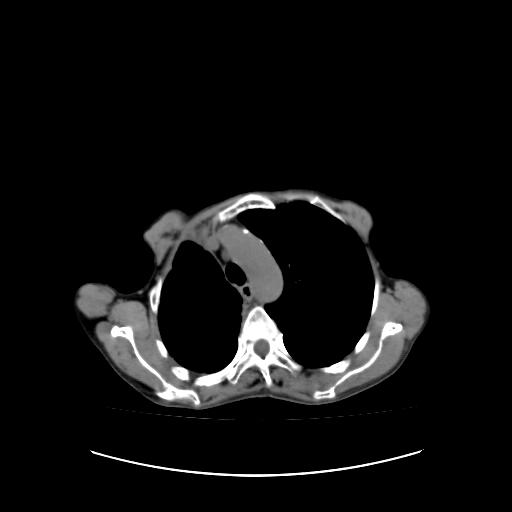

右侧胸膜增厚,局部呈结节状增厚,右侧胸腔少量积液。双肺未见确切肿块影。纵隔未见淋巴结肿大。气管、支气管通畅。考虑右侧胸膜间皮瘤(恶性?)可能性大。不除外癌性胸膜炎。

右侧胸廓塌陷,右侧胸膜广泛增厚并见多发胸膜结节,右侧少量胸腔积液并包裹。

右侧广泛胸膜增厚,局部呈结节状增厚,右侧胸腔少量积液。双肺未见确切肿块影。纵隔未见淋巴结肿大。气管、支气管通畅。考虑右侧胸膜间皮瘤(恶性?)可能性大。支持!